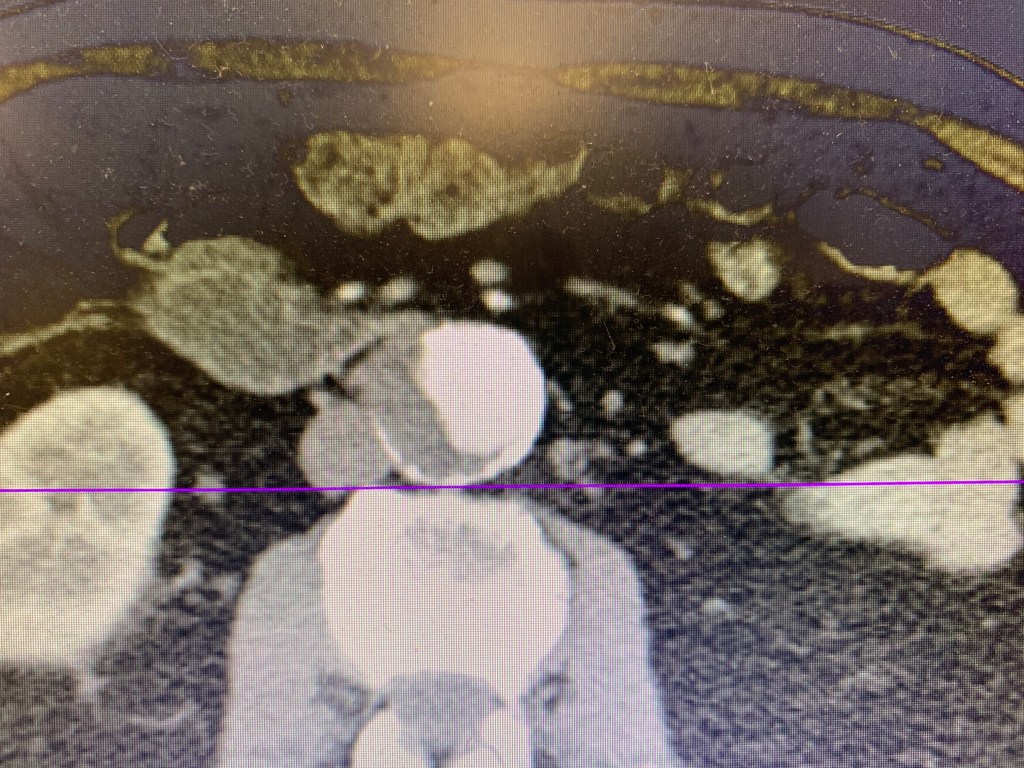

Color shows there are two areas in the aorta, one with flow and one with no flow concerning for potential dissection vs thrombus. CTA of the abdomen and pelvis is obtained and shows:

CT shows a AAA without rupture. There is an area of thrombus seen on the CT which correlates with the ultrasound findings seen above. There is no true dissection flap.